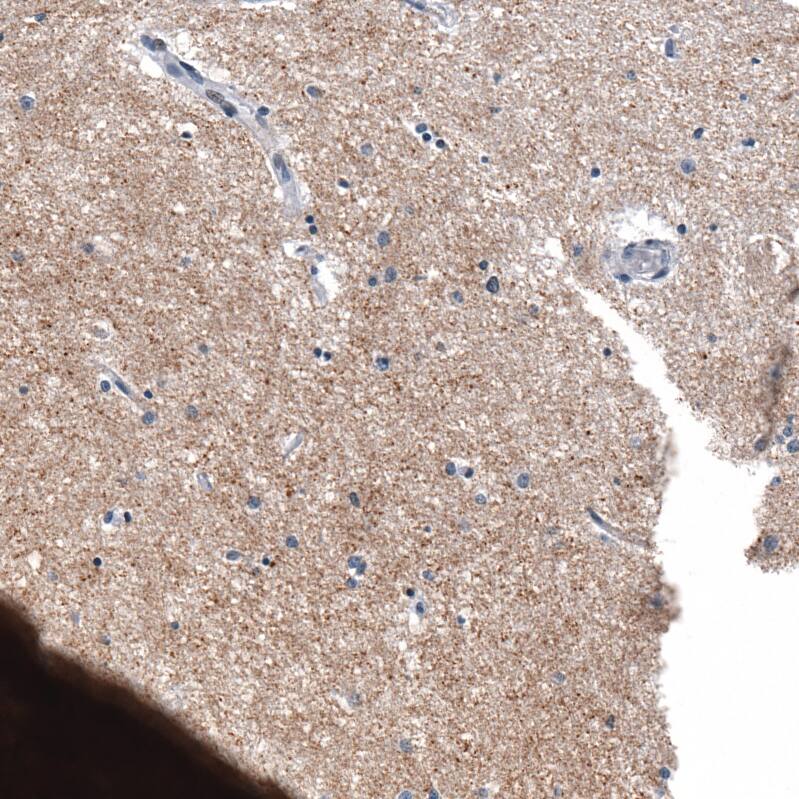

Staining of human cerebral cortex shows moderate cytoplasmic positivity in neuropil.